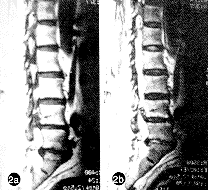

磁共振成像可以提供矢状面、横断面、冠状面的影像。本组MRI正确诊断率为85%,其中矢状面断层更为有效。2例漏诊者均为矢状面断层未经过椎间孔层面,另1例旁正中切面过于稀疏,漏扫了突出部位。作者认为,MRI也是一种敏感、可靠的手段,特别是矢状面断层可直接显示椎间盘自椎间隙水平向上移位的程度,弥补了CT的不足。提高诊断水平的关键是矢状面断层一定要包括椎间孔。在经椎间孔的矢状面断层上,椎间孔内原有的高信号影像消失,代之以与椎间盘同信号(低信号)的影像,或者占据椎间孔的下部,或者占据整个椎间孔,有时可见到椎间盘信号自间隙向头侧延伸(图2a、2b,插Ⅲ)。横断面表现与CT相似(图2c,插Ⅲ)。MRM不需要在蛛网膜下腔注入造影剂而使整个硬膜囊显影,可以清楚显示冠状面上的组织影像。经过神经根纵轴的冠状面可以显示神经根全长及其与周围结构(如椎间盘)的关系。与其它影像学相比,这是其独特之处。如果间盘仅突出于椎间孔或椎间孔外,可见突出的间盘自与椎体同序数的神经根的下方挤压之,使神经根的信号完全中断或部分中断;如果合并后外侧突出,可见间盘信号同时压迫上下两根;如合并中央型突出,还可见马尾神经的压迹(图3,插Ⅲ)。本组MRM 5例均获正确诊断,较所有其它影像学手段更加直观。作者认为MRM可能是诊断椎间孔与椎间孔外腰椎间盘突出症最好的方法。既往无MRM用于腰椎间盘突出症诊断的报告,本组例数较少,有关其诊断价值有待进一步积累资料证实。

图2 L4~5左侧椎间孔内椎间盘突出症的MRI影像 a 经腰椎椎间孔区矢状面断层显示突出于左侧椎间孔内之巨大间盘(箭头所示),原椎间孔内的高密度影消失,突出间盘占据椎间孔全部;b 经旁正中矢状面断层显示突出间盘自椎间隙向头侧延伸;c 经椎弓根下缘横断面显示椎间孔内突出的间盘(箭头所示)及被挤向内侧的神经根(L4),三角所示为对侧正常的L4神经根